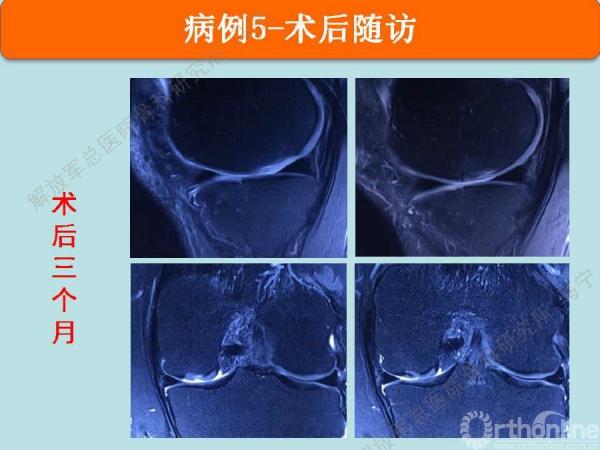

病例5

术中显示损伤部位及第四代组织工程软骨修补术后。术后三个月核磁显示组织工程软骨具备一定厚度,胶原含水量接近正常,还存在GAP现象。随访还在进行中。